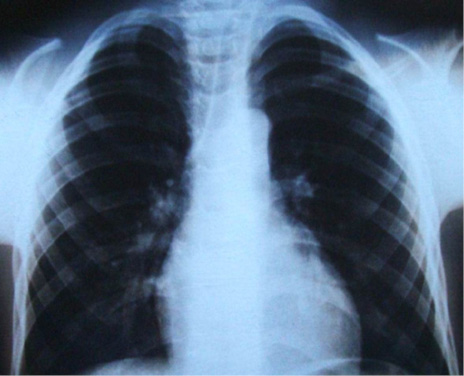

En el estudio imagenológico se observó en la radiografía de tórax, hipoplasia clavicular bilateral y tórax en forma de campana (Figura 2), en la radiografía panorámica se mostró la presencia de once dientes supernumerarios en el maxilar y nueve en la mandíbula (Figura 3), en la radiografía lateral cráneo se observó presencia de huesos wormianos landoideos (Figura 4); en la radiografía carpal se observó longitud simétrica de las falanges y sin alteraciones (Figura 5), de acuerdo con los hallazgos encontrados en el examen físico y la evaluación radiológica, se realizó la impresión diagnóstica de displasia cleidocraneal.

Figura 2. Radiografía de tórax donde se observa hipoplasia clavicular y tórax en forma de campana. Fuente: autores.